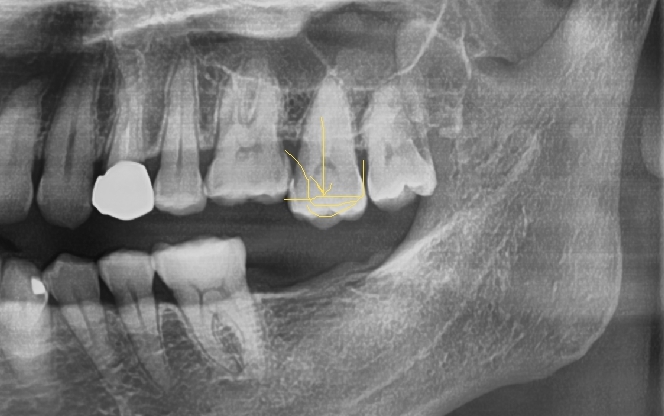

![[서울시청역치과] 20대, 30대도 임플란트를 하나요?? +네비게이션임플란트안내 관련 이미지 3](https://pub-9f2bb3498faf4d1d8714b41df24753e3.r2.dev/content/clinics/archive/rseeanjxfu/naver_blog/yonseiyegam/assets/by_hash/90a82f3881cd93a8b2bf1efa3d96800f7ef6539536a0d836fe5acf7eae00345e.jpg)

위의 경우는 임플란트를 제때 하지 않아 뒤의 치아가 앞으로 쓰러져서

임플란트를 위한 적절한 공간이 남아 있지 않습니다.